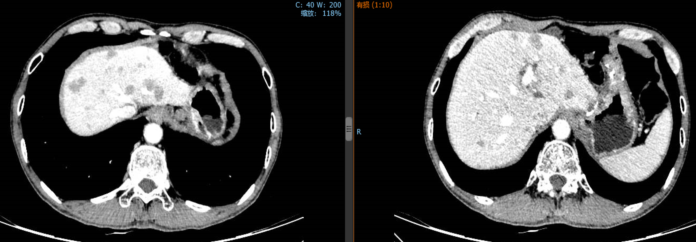

2018年10月23日至2019年2月3日行顺铂+氟尿嘧啶联合赫赛汀方案治疗5周期,疗效评估PR。

2019年1月24日,经4个周期赫赛汀+DF后,患者肝脏转移灶明显缩小。

2018年10月17日,化疗前

2019年1月24日,化疗后